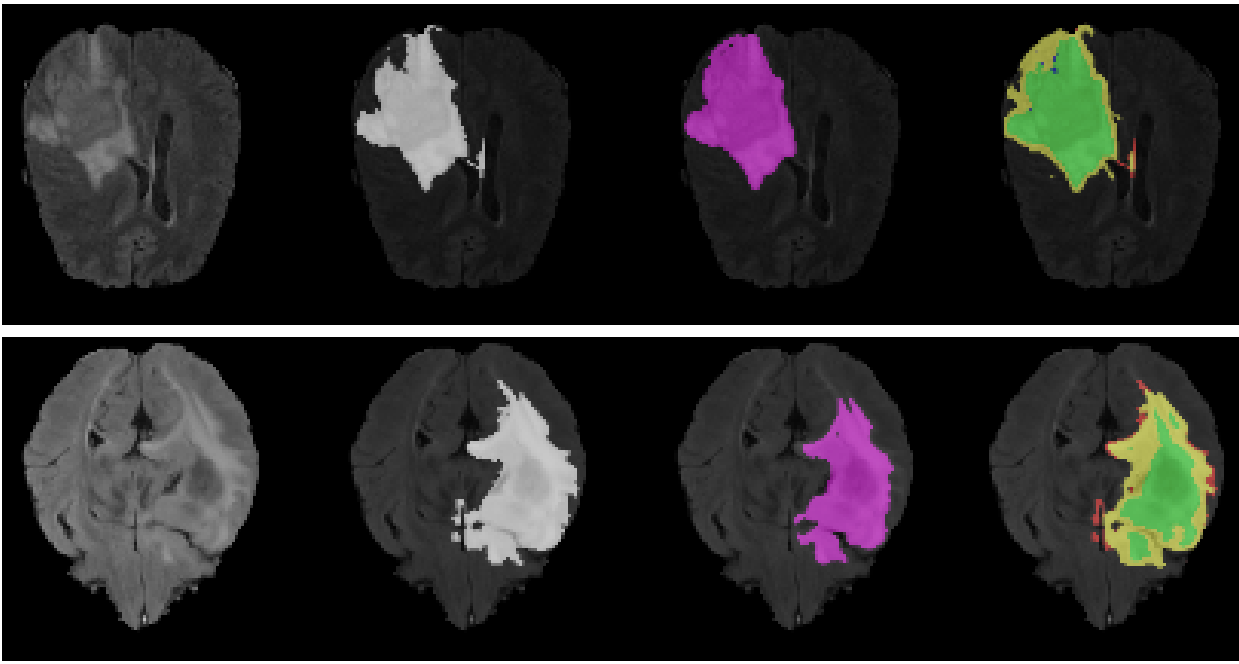

This might sound like a contrived example not related to AI, but we face exactly the same challenges in AI as well. I think the most natural starting point is to discuss the public challenges & competitions in AI evaluations which I have had the fortune to co-lead, help create and run at NeurIPS, MICCAI, & ICLR1. As a concrete example, I will use the challenge we organised at MICCAI on uncertainty estimation in brain tumour segmentation2. In the challenge, participants were invited to submit new AI tools for brain tumour segmentation—where participants' AI systems are given MRI scans of patients with brain tumours, and the AI's job is to say where the tumour is. The task of uncertainty estimation specifically involves highlighting where it is that the AI system is uncertain about a tumour—for example the system might confuse normal tissue with a tumour, and we don't want the neurosurgeon to use that false tumour in their surgery plan.

In the brain tumour challenge the first step was to design a metric of safety. This is some quantity that would tell us whether the AI tool submitted by a participant actually does what we want it to do. How do we define what it is that we want the AI to do? well, this turned out to be a really difficult task... A naive starting point was to say "the AI should not falsely classify normal tissue as a tumour". But if we do that then we open a loophole—the AI could just always say "no tumour". In that case, we can dictate "the AI should still classify tumours but not falsely classify normal tissue as a tumour". But now, what if the AI managed to classify all tumours perfectly and only falsely classified as a tumour a single bit of normal tissue at the other side of the brain that doesn't affect the surgeon's surgery plan? Long story short, we had many back and forth meetings improving the metrics and finding new loopholes in our evaluation, and matured this into our first iteration of the public challenge.

But this was only the first step in our journey. As we deployed our evaluation as a public challenge, like with the car story above, participants were incentivised to find new loopholes in our metric and artificially maximise the safety metric without actually building safer AI tools3. This led us to iterate over the metric design and improve it for the following year's public challenge, playing a cat-and-mouse game with our "adversaries", trying to pre-emptively find exploits in our metric of safety before participants could artificially inflate their score without actually building safer AI tools.